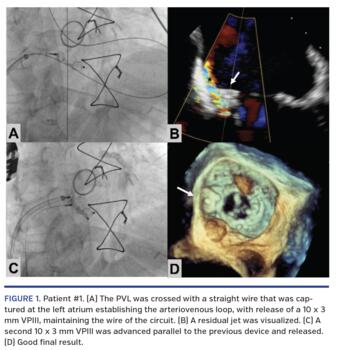

Patient #1. A 69-year-old male with history of aortic SVR and coronary artery bypass graft had endocarditis, and therefore underwent surgical implantation of a biologic mitral prosthesis and a mechanical aortic prosthesis. The immediate course was complicated with refractory HF secondary to severe mitral regurgitation (MR) generated by a posterior PVL. The heart team decided on percutaneous closure, which was performed on day 8 post surgery. The PVL was crossed with a straight wire that was captured at the left atrium, establishing the arteriovenous loop, with release of a 10 x 3 mm Amplatzer Vascular Plug III (VPIII; Abbott Vascular), maintaining the wire of the circuit (Figure 1A). A residual jet was visualized (Figure 1B and Video 1), so a second 10 x 3 mm VPIII was advanced parallel to the previous device (Figure 1C) and released with a good result (Figure 1D and Video 2).